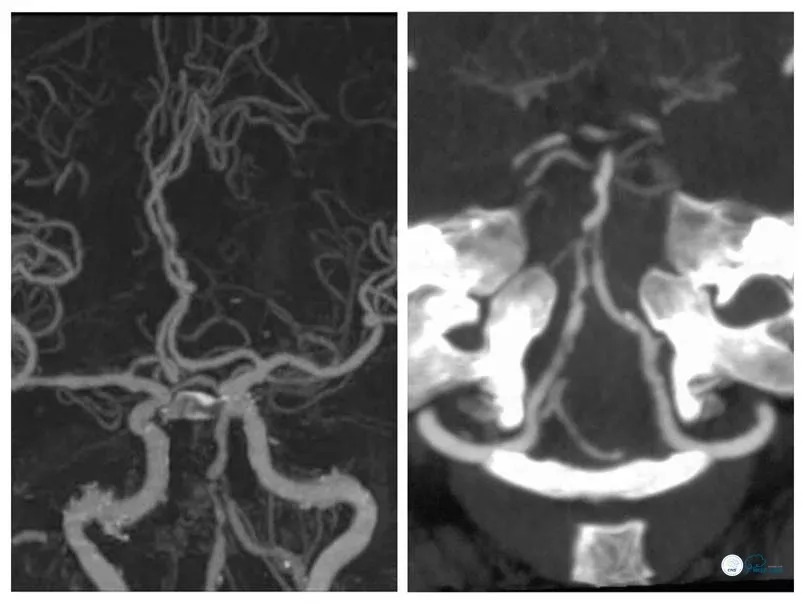

患者,女 ,61岁,主因“反复头晕5月余”入院。患者5个月前无明显诱因出现头晕、每次持续半小时左右,无其他伴随症状和体征,在当地医院就诊行头颅磁共振检查未见新发脑梗死(图1)。

图1

MRA及CTA示右椎动脉优势,双椎动脉V4段-基底动脉汇合处狭窄(图2、3)。

图2